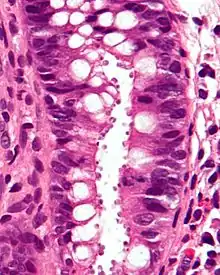

Micrograph showing cryptosporidiosis. The cryptosporidium are the small, round bodies in apical vacuoles on the surface of the epithelium. H&E stain. Colonic biopsy.

Other staining techniques include acid-fast staining,[26] which will stain the oocysts red.[25] One type of acid-fast stain is the Kinyoun stain.[21] Giemsa staining can also be performed.[22] Part of the small intestine can be stained with hematoxylin and eosin (H & E), which will show oocysts attached to the epithelial cells.[25]